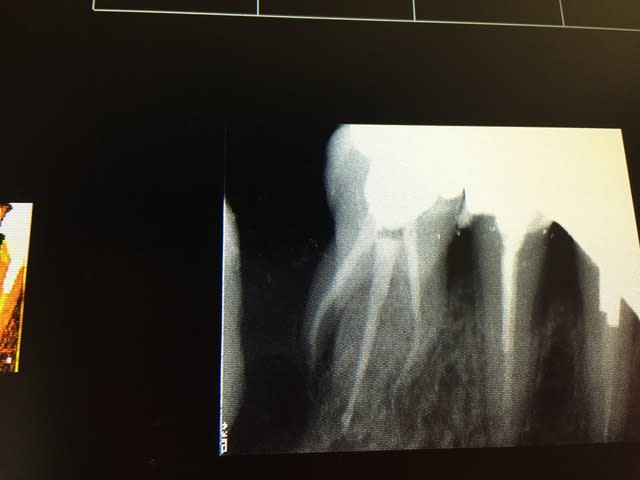

Evidemment que s'il y a pulpite il faut faire la bio... Mais s'il n'y en a pas pourquoi ne pas laisser une chance de plus à une dent?

Je n'ai jamais dit que coiffage/ collage c'est automatique ni en tout point supérieur... tout comme l'inlay core couronne ne l'est pas.

Je dis juste que l'indication médicale devrait primer et pas celui du remboursement.

Je ne veux pas dévitaliser une dent parce que j'ai besoin de faire accepter un devis inlay core couronne pour faire ma marge.

je veux dévitaliser une dent parce que j'y suis médicalement ou techniquement obligé.

Après je suis pas aussi bon que toi en endo mais il m'arrive de ne pas faire que de la merde :D (d'ailleur on peut voir que le collage ça merde aussi :D)